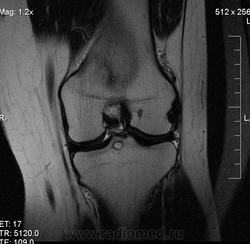

Пациентке 26 лет, левый коленный сустав. Жалобы на боли в обоих коленных суставах с 13 лет (больше в левом), преимущественно "стартовые" боли, в последние месяцы беспокоят чаще, ночью не болит, повышение температуры не отмечает. Cмущает небольшая зона перифокального отека вокруг кистовидной зоны -киста с перифокальным отеком костного мозга? остеоид-остеома? абсцесс Броди мне кажется менее вероятен. КТ в этом случае сможет помочь?

Fig. 22. Subchondral cyst. (A) Chronic lateral knee pain in 23-year-old man. Radiograph shows well-defined radiolucency in the lateral tibia representing a cystic lesion (arrow). (B) Sagittal PD FS image shows well-defined subchondral cyst (arrow) with surrounding BML (arrowheads). Cyst not associated with OA.

Спасибо, nnemo. Не нравится только небольшой отек по периферии кисты, интересно за счет чего?

отек может сопровождать дегенеративные кисты.

"MR: homogeneous high signal intensity on T2 WI due to the synovial fluid within the lesion. Usually no or limited edema."